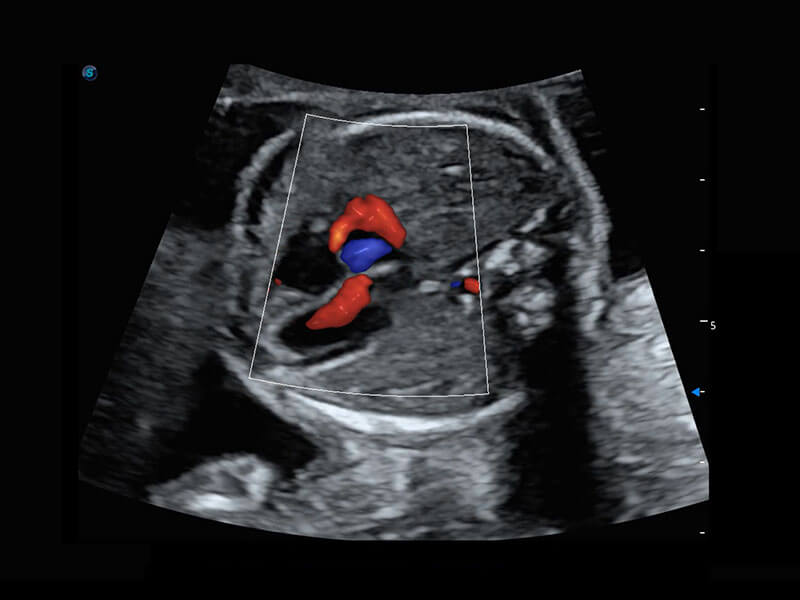

四腔切面

四腔心血流